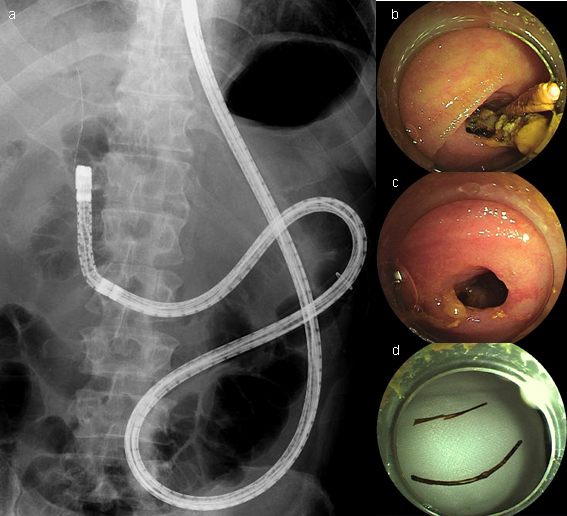

ダブルバルーン内視鏡(図1)は、内視鏡先端とオーバーチューブ先端にバルーンが装着されていて、これら二つのバルーンで腸管を軽く把持して短縮しながら腸管内を内視鏡が挿入される構造になっています。シングルバルーン内視鏡(図2)は、オーバーチューブ先端のみにバルーンが装着されていて、内視鏡には装着されていませんが、基本的な挿入原理は同じです。

3. バルーン内視鏡を用いたERCPの実際